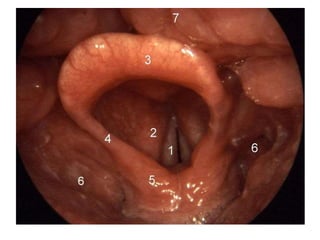

• #14 Larynx. 1=vocal folds, 2=vestibular fold, 3=epiglottis, 4=plica aryepiglottica, 5=arytenoid cartilage, 6=sinus piriformis, 7=dorsum of the tongue.